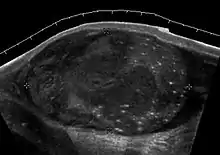

Seminoma is the most common tumor type in cryptorchid testes. The risk of developing a seminoma is increased in patients with cryptorchidism, even after orchiopexy. There is an increased incidence of malignancy developing in the contralateral testis too, hence sonography is sometimes used to screen for an occult tumor in the remaining testis. On US images, seminomas are generally uniformly hypoechoic, larger tumors may be more heterogeneous [Fig. 3]. Seminomas are usually confined by the tunica albuginea and rarely extend to peritesticular structures. Lymphatic spread to retroperitoneal lymph nodes and hematogenous metastases to lung, brain, or both are evident in about 25% of patients at the time of presentation.